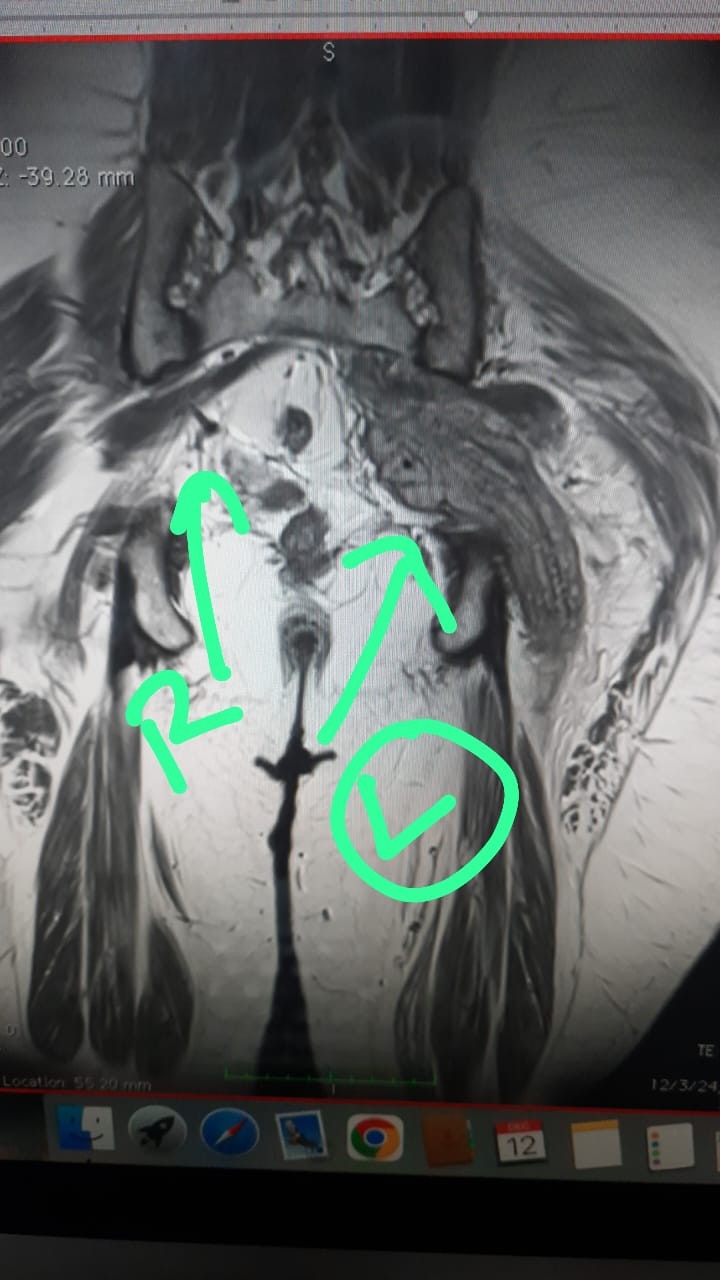

MRI – Hyperintense lesion in the sciatic nerve along the L4, L5, and S1 fibers, starting in the retroperitoneum and extending beyond the greater sciatic foramen. Approximate length was 20 cm (Figs. 1 and 2).

Figure 1: Magnetic resonance imaging scan T1 image OD sciatic nerve showing thickened with a fusiform appearance. The green arrow marled (L) in image shows the tumour while the marke (R) shows normal sciatic nerve.

Figure 2: Magnetic resonance imaging scan T1 image showing hyperintensity along the course of sciatic nerve.